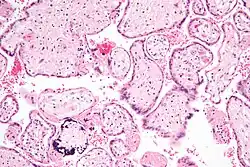

Micrograph of CMV placentitis -